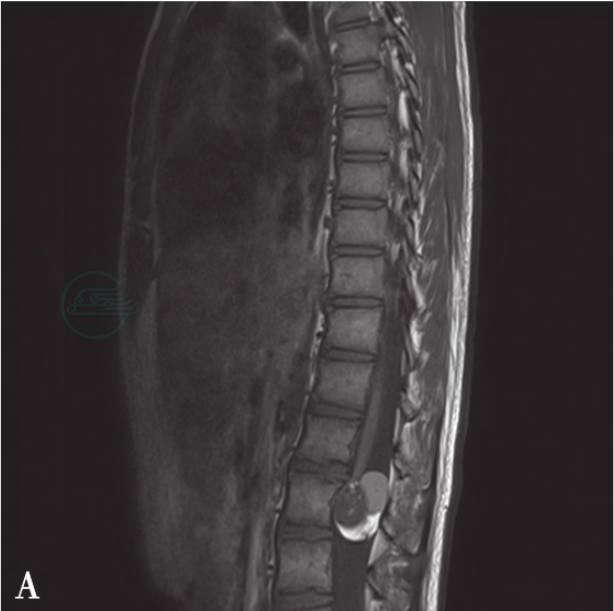

MRI示肿瘤呈卵圆形,因有多种组织成分,信号混杂(图1),T1WI及T2WI均可显示高信号脂肪组织,脂肪抑制序列呈低信号。如为出血则仍呈高信号。瘤内钙化灶T1WI、T2WI均显示低信号,小的钙化灶通常显示不清。囊性畸胎瘤MRI表现与皮样囊肿、表皮样囊肿相似。

图1 畸胎瘤

A、B:平扫矢状位肿瘤混杂信号,边界清楚,其内见片状双高信号脂肪组织